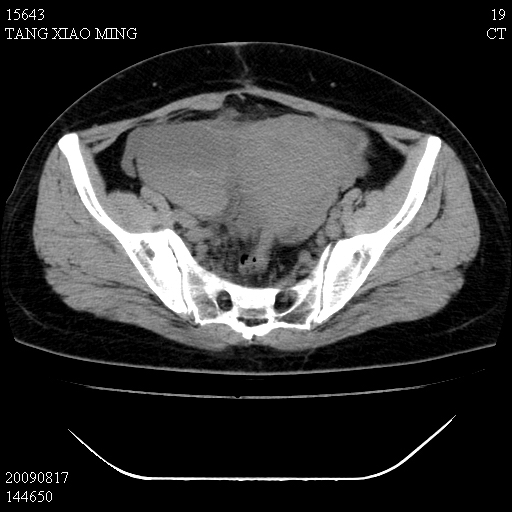

标题: CT21692:盆腔病变

女,33岁,右下腹痛2年余,既往宫外孕病史,如在我院手术,结果下周公布,

可能的诊断。1子宫内膜异位【子宫腺肌症并右卵巢巧克力囊肿】;2 右卵巢囊腺瘤。子宫肌瘤

1)考虑卵巢巧克力囊肿,不排除卵巢囊腺瘤。2)子宫肌瘤可能。

卵巢囊腺瘤,子宫肌瘤,直肠壁厚,不除外占位.